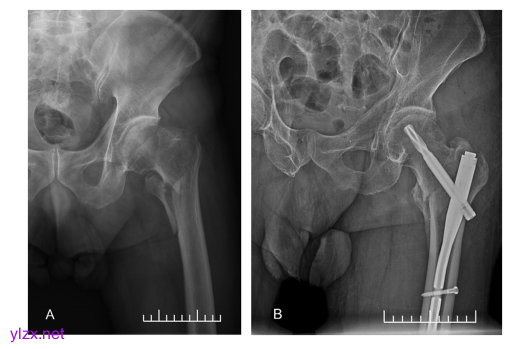

股骨粗隆间骨折内固定术。(A)术前额部X线片。(B)术后额部X线片